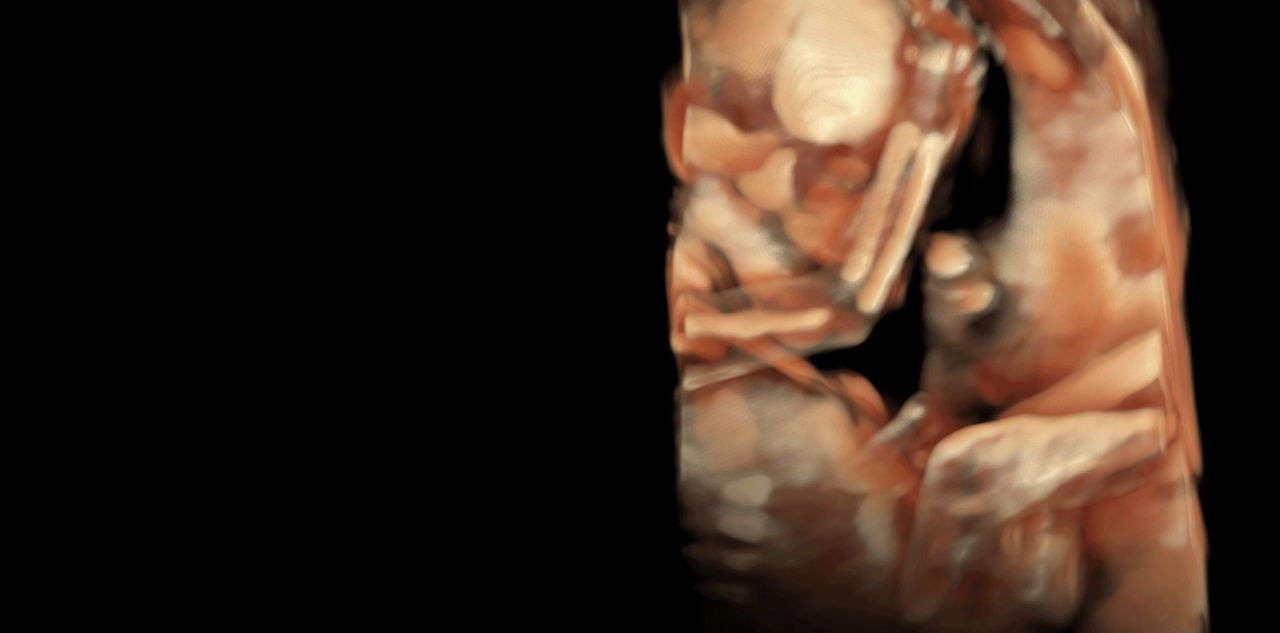

Expand Imaging Capabilities

Faster.Sharper. Clearer.

Faster.Sharper. Clearer.

A World of Possibilities